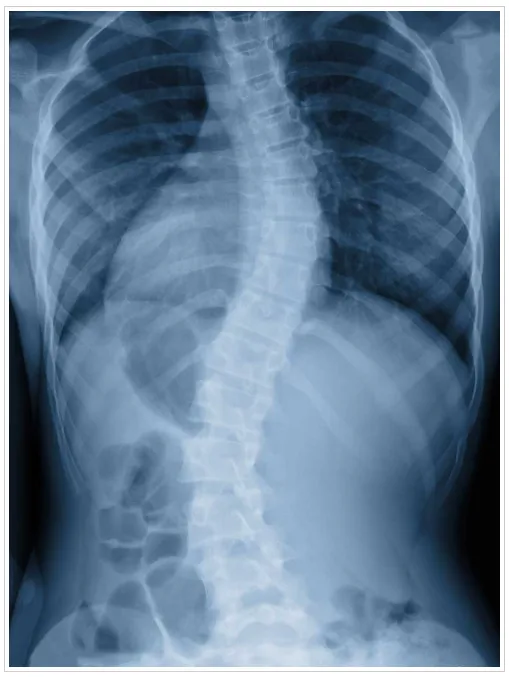

When detected early, scoliosis can be managed and treated to prevent the problem from getting worse. With scoliosis, the spine has abnormal curvatures to the side or even twists. Most cases of scoliosis appear for unknown reasons as scoliosis tends to develop before puberty in adolescence, in children who previously had no spine issues.

Many cases of scoliosis do not require surgery or extensive treatment, but if the curvature becomes more severe, medical intervention may be needed. Scoliosis appears equally in boys and girls, but typically girls are more likely to develop significant curvature that warrants treatment.